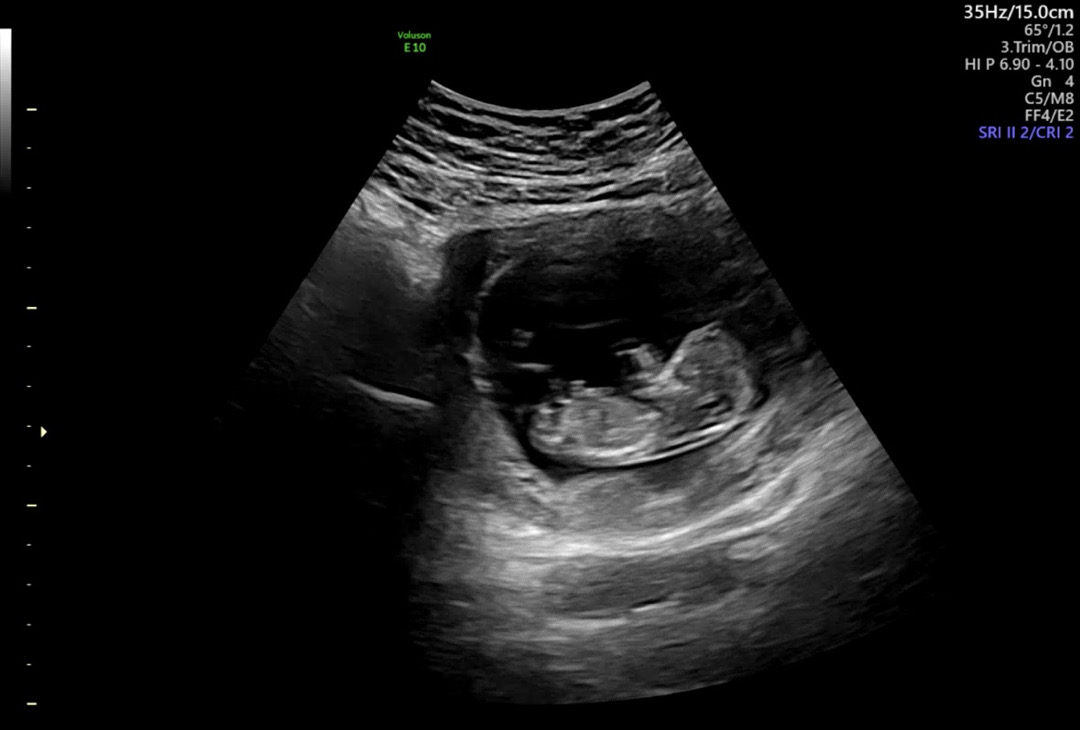

12주차 초음파 성별

안녕하세요!! 12주 2일차 각도법 투표부탁드려요💛